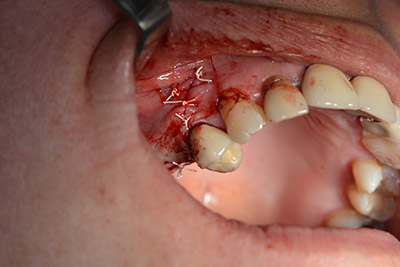

Danach wird das Implantat eingebracht und der Knochen aufgebaut. Aufgrund der Größe des Augmentates wurde im vorliegenden Fall Eigenknochen, der als Bohrspäne bei der Implantation 16 und der Fenestration 14 angefallen ist und mit einer Knochenfalle aufgefangen wurde, mit Knochenersatzmaterial vermischt.

Eine resorbierbare Membran bildet die Barriere nach bukkal und deckt das Augmentat ab. Zum Schluss wird speicheldicht vernäht. (Abb. 15 bis 19).